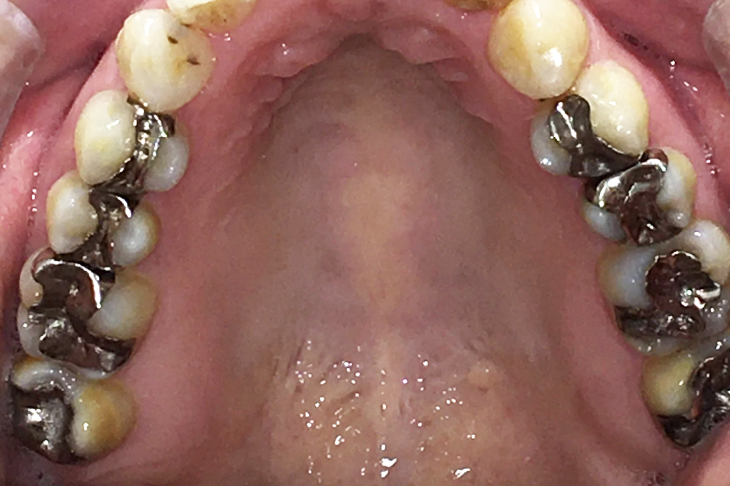

セラミックインレーと

ジルコニアインレーの症例

Before

部位拡大写真

After

基本情報

| 年齢・性別 | 40代・女性 |

|---|---|

| 主訴 | 虫歯気になる 全体的に銀歯をやりかえたい 右上4567 |

| 治療内容 | セラミックインレー(右上456番) ジルコニアインレー(右上7番) |

| 治療費 | 209,000円 (セラミックインレー1本55,000円) (ジルコニアインレー1本44,000円) |

| 治療期間 | 約2週間 |

| リスク・副作用 | ジルコニアインレーは硬いため噛み合わせの歯を傷付ける可能性がある |